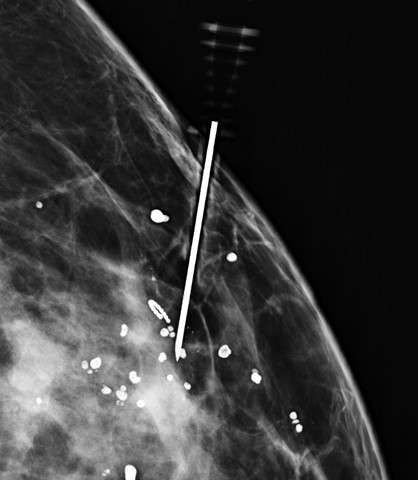

Technologist obtains orthogonal image of the breast (Figure 3).

Radiologist adjusts needle depth and then deploys wire, with tip between 0.5 – 1.0 cm deep to the lesion or as indicated based on surgeon preference. An image is taken to confirm wire tip location, then the needle(s) may be removed.